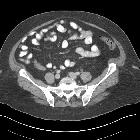

Mucinous neoplasms can lead to abdominal pain, gastrointestinal obstruction, and abdominal distension when the complication pseudomyxoma peritonei has developed.

- Mukozele der Appendix

- muzinöse Neoplasien der Appendix

- muzinöses Zystadenokarzinom der Appendix

- appendiceal mucinous cystadenoma

- appendiceal mucinous adenocarcinoma